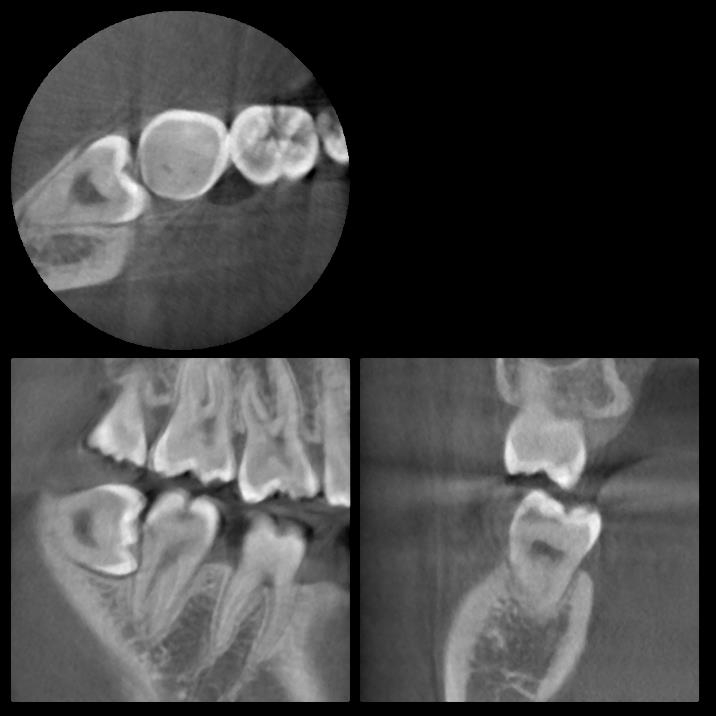

レントゲン写真の状態を御覧ください。

部位:右上8番埋伏歯

部位:右下8番埋伏歯

CT画像で状態を確認し、親知らずの歯根の曲がり具合や歯根の太さ、

下の親知らずの場合は下歯槽管神経との距離、

位置関係や骨の厚みなどを確認します。

下歯槽神経を傷をつけないように注意が必要です。

この場合、神経との距離を測り慎重に抜歯しないといけません。